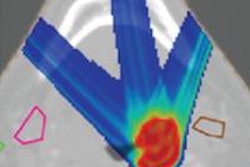

Left: PCA motion prediction using 2D fiducial markers. Right: PCA prediction using either tracked diaphragm SI-motion or 2D markers motion as predictor.

Left: PCA motion prediction using 2D fiducial markers. Right: PCA prediction using either tracked diaphragm SI-motion or 2D markers motion as predictor.The researchers examined the accuracy of their motion reconstruction by comparing the predicted results with the ground-truth motion (extracted directly from the 4D MRI data). Averaged over all 11 subjects, for 99% of predicted positions, median (maximum) errors were better than 2.63 (5.67) mm when tracking fiducial markers. Results were similar for tracking diaphragm motion, which resulted in a median (maximum) 99% prediction error of 2.7 (4.2) mm.

To study the feasibility of the proposed motion reconstruction scenario, Zhang and colleagues extracted motion data from 4D MRI liver studies of 11 volunteers, over 130 continuous breathing cycles (with 10 time steps for each cycle). They used the first 1,000 time steps to compute patient-specific motion models for each of the 11 subjects and the remaining 30 breathing cycles to generate simulated 4D CT datasets.

From these time-resolved CT images, the researchers generated digitally reconstructed radiographs (DRRs), using the geometric parameters of the BEV system and the tumor location with respect to the gantry isocenter. They then used tracking algorithms to extract the motion of the diaphragm or fiducial markers, as visualized in the DRRs. Finally, based on these tracked surrogate motions and the patient-specific motion models, they predicted the 3D deformable motion in the liver region for each subject.